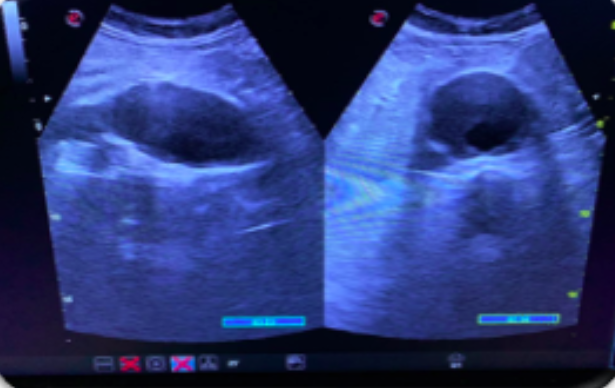

Los estudios de morbimortalidad reflejan que la enfermedad cardiovascular ocurre en más del 50% en varones y un 80% en mujeres catalogados de RCV bajo o moderado. En estudios sobre IAM el 50% de ellos presentaban uno o ningún FRCV. Así, podemos decir que existe un debate abierto sobre si las guías actuales infraestiman la arterioesclerosis ya existente, por lo que nos planteamos esta experiencia con la exploración ecográfica. Para ello realizamos una rotación en una unidad de RCV hospitalaria, con un protocolo específico para luego aplicarlo en el Centro de Salud. La valoración es similar a la utilizada en el Estudio PESA, donde se evalúa la existencia de placas de ateroma a nivel femoral, carotídeo, además de despistaje de aneurisma de aorta abdominal.

La ecografía es útil para valorar la arterioesclerosis mediante la detección de placa de ateroma en arterias carótidas y/o arterias femorales, indicando lesión de órgano diana (LOD) y llevándonos a facilitar la decisión de intensificar el tratamiento y así poder modificar la progresión de la enfermedad.

Implementar la ecografía clínica en la consulta del médico de familia para conseguir una valoración más precisa del RCV, mediante la detección de placa de ateroma y aneurisma de aorta abdominal, mejorando la atención y la valoración del RCV de nuestros pacientes ofertando la ecografía de forma protocolizada. Además de concienciar a la población sobre su patología, la necesidad de una prevención precoz y así poder frenar su progresión.